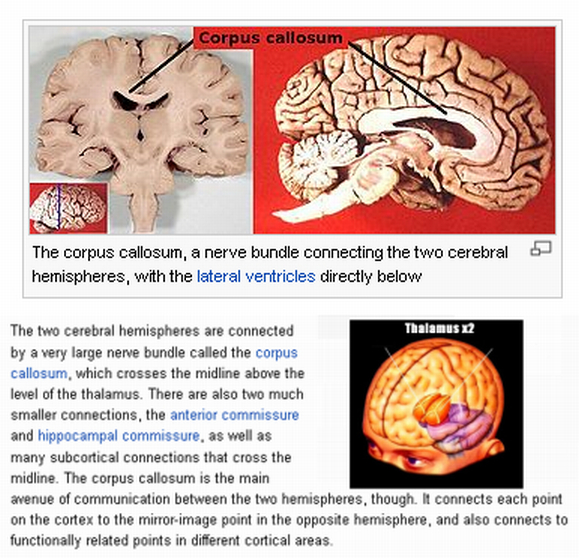

The thalamus has two lobes known as the ‘thalamic bodies,’ which look like a smaller version of the two hemispheres of the brain known as the cerebrum.

The thalamus has multiple functions. It may be thought of as a kind of switchboard of information. It is generally believed to act as a relay between a variety of subcortical areas and the cerebral cortex. In particular, every sensory system (with the exception of the olfactory system) includes a thalamic nucleus that receives sensory signals and sends them to the associated primary cortical area.

The cerebral cortex is the outermost sheet of neural tissue of the cerebrum of the brain in some vertebrates. It covers the cerebrum and cerebellum, and is divided into left and right hemispheres. The cerebral cortex plays a key role in memory, attention, perceptual awareness, thought, language, and consciousness.